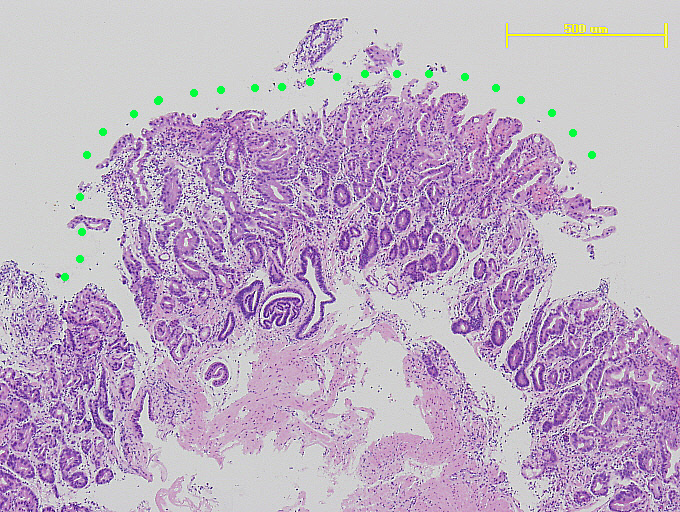

ヘマトキシリン・ エオジン染色されたプレパラート

- 診断作成されたプレパラートを顕微鏡で観察し、診断いたします。診断書を作成し、主治医に報告します。